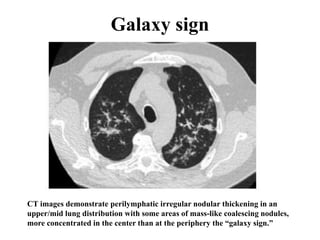

Galaxy sign

CT images demonstrate perilymphatic irregular nodular thickening in an

upper/mid lung distribution with some areas of mass-like coalescing nodules,

more concentrated in the center than at the periphery the “galaxy sign.”

-Grouped nodules or coalescent nodules

surrounded by multiple satellite nodules (Galaxi

sign)